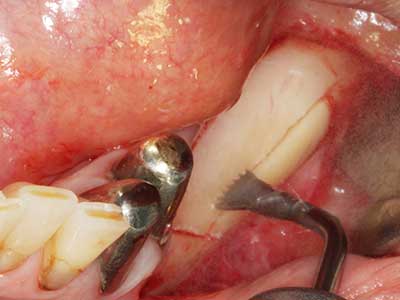

Indication: Bone splitting

Bone tissue is not simply a mineral structure but also contains a substantial proportion of collagen fibres. This means it not only has good compressive strength but also a degree of flexibility, which can be taken advantage of when performing bone augmentations. In the classical expansion procedure using bone splitting, the atrophied alveolar ridge is split longitudinally and carefully expanded after reaching an adequate osteotomy depth (Fig. 13-16), ideally without substantial removal of the periosteum (Brugnami, Caiazzo et al. 2014, Stricker, Fleiner et al. 2014). Screw and plate systems with increasing expansion distance have proven effective in separating the two bone lamellae while remaining below the fracture threshold. In general, residual bone widths of at least 3–4 mm are required (Chiapasco, Zaniboni et al. 2006) to guarantee adequate flexibility and sufficient bone coverage of the future implants. If necessary, a vertical relief osteotomy on one or both sides can improve flexibility. A combination with additional augmentation techniques, particularly on the buccal side, has been described as an alternative to the classical technique.

The splitting procedure is particularly atraumatic and there is no significant loss of dimension when using piezosaws, and there are no significant differences between implants in split jaws and implants in an alveolar ridge without a bone deficit (Chiapasco, Zaniboni et al. 2006, Danza, Guidi et al. 2009). However, sufficient continuous irrigation is essential, particularly with locally restricted and deep splitting to prevent thermal stress in the apical osteotomy regions.